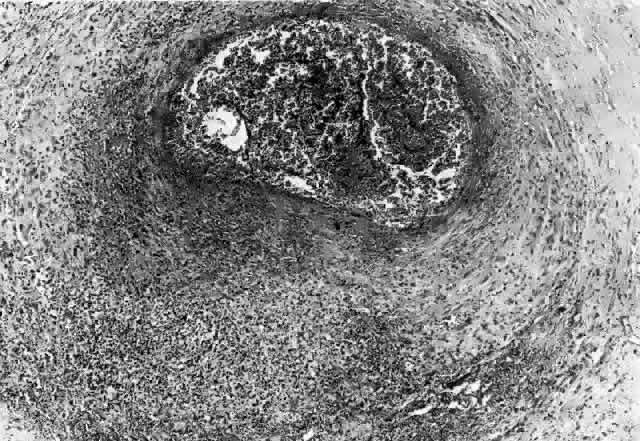

Wegener's granulomatosis is characterized by inflammatory lesions of the upper respiratory tract, lower respiratory tract, the kidneys, and, to varying degrees, generalized small vasculitis of other structures, including the eye (Figs. 10 AND 11). The definitive diagnosis is confirmed by biopsy. A limited form of the disease has been described that spares the kidneys.

Fig. 10. A. This 68-year-old woman presented with acute orbital inflammation, pain, and diplopia. Clinical evaluation demonstrated a medial orbital mass. Biopsy of the orbital mass demonstrated significant vasculitic and granulomatous changes believed to be consistent with Wegener's granulomatosis. No systemic disease was present. B. Appearance of same patient after treatment with prednisone and cyclophosphamide demonstrating complete resolution of the inflammatory process.

Fig. 11. A. This 31-year-old man has had Wegener's granulomatosis for 2 years. His disease process is stable on chronic corticosteroid therapy. He has no evidence of systemic disease. Note right-sided proptosis and hyperglobus. B. Profile of same patient demonstrating collapse of nasal bridge from bony destruction secondary to Wegener's granulomatosis. Note presence of swelling in lower eyelid. C. Axial CT image from the same patient demonstrating significant bilateral disease and bony destruction. Despite the extent of the orbital process on the right, the patient does not have diplopia. D. Coronal CT image showing destruction of medial orbital walls, vomer, and orbital septum. E. Pulmonary biopsy specimen from patient with orbital signs contains an almost obliterated vessel to right of center and scattered giant cells on left (H&E, ×160).

Ocular manifestations include orbital inflammation, scleritis, keratitis, and uveitis. The ocular involvement can occur from extension of sinus and nasal lesions or from focal small vessel vasculitis.

Ocular Manifestations

Ocular involvement of Wegener's granulomatosis occurs as a result of contiguous spread from the upper respiratory tract and from focal small vessel vasculitis involving ocular structures. Proptosis, orbital pain, limitation of extraocular movement, and periocular edema suggest orbital involvement. The orbital presentation may be identical to that of idiopathic orbital pseudotumor except that bilateral presentation is more frequent in Wegener's granulomatosis and other vasculitides.3

Orbital involvement may be the initial or presenting manifestation of the disease or may follow known upper respiratory tract and sinus involvement. In severe cases optic nerve compression, optic disc edema, retinal vascular congestion, and exposure keratopathy may occur. The optic nerve may also be directly involved by the vasculitic process. Orbital cellulitis may occur in association with sinusitis.42 The orbital inflammation may be rapidly progressive, requiring surgical decompression in addition to systemic therapy.42 However, the surgical intervention has also been associated with flare of the disease and healing difficulties because of active vasculitis. As a general rule, surgery should be avoided until the inflammatory process is brought under control by aggressive medical treatment.

Laboratory Findings

Wegener's granulomatosis is a biopsy diagnosis. However, even in patients with a well-documented diagnosis of Wegener's granulomatosis, orbital biopsy may not demonstrate the classic features of vasculitis, granulomatis inflammation, and tissue necrosis in as many as 50% of cases.83 Orbital biopsy has also been associated with recurrence of orbital inflammation.3 Biopsy of a nasal lesion is more likely to demonstrate granulomatous inflammation with giant cells than an orbital biopsy from the same patient.83 A thorough search for other lesions and the gathering of ancillary laboratory and imaging studies is imperative before proceeding with orbital biopsy. Consultation with other specialists is highly advisable.